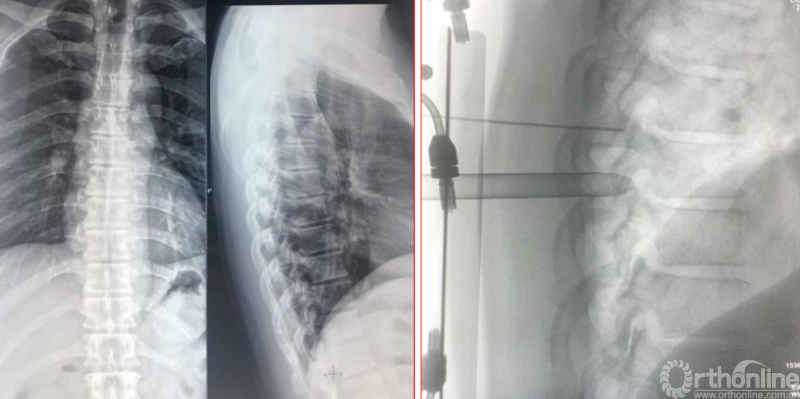

术前资料

术后影像学资料

术后第二天资料